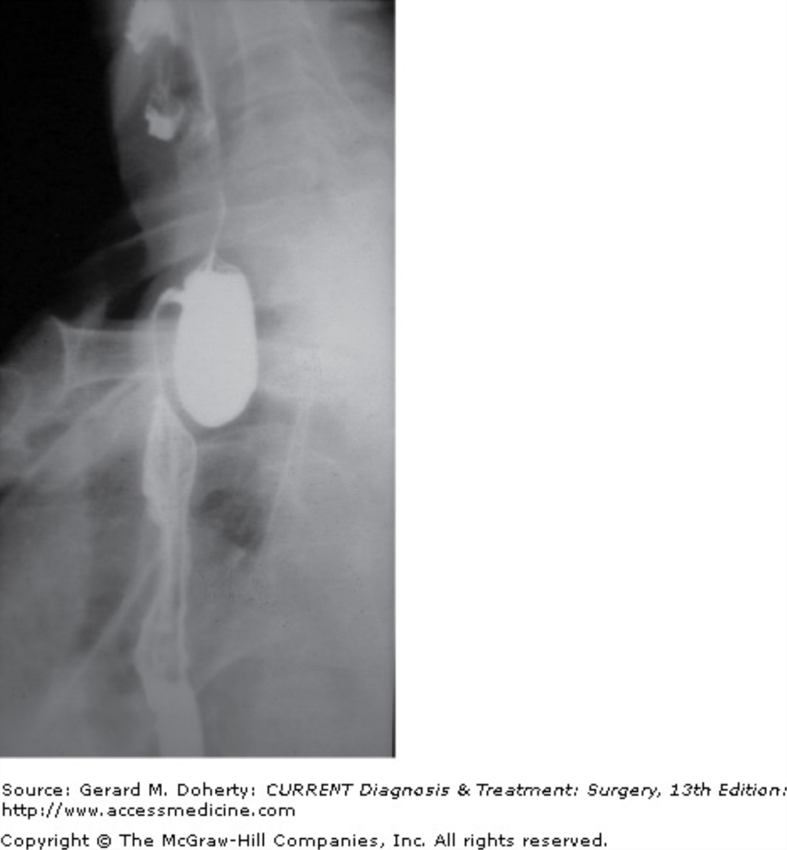

What do you see?

Zenker Diverticula